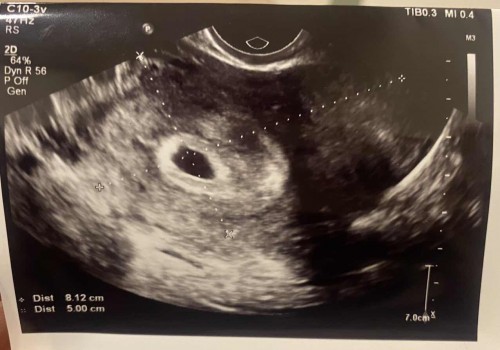

ปวดมาก แล้วกังวลไปหมด ปวดแบบจี้ดๆ ข้างซ้าย เลยกังวลจะท้องนอกมดลูกหรือเปล่า วันนี้เลยไปซาวด์มาแล้วค่ะ สรุปพบถุงตั้งครรภ์ในมดลูกปกติ หมอบอกตำแหน่งที่ปวดไม่ใช่ตำแหน่งปีกมดลูก โล่งอกมากๆ ตอนแรกกังวลไปหมดเลย เจอตัวน้องตอนกี่วีคกันบ้างคะ ของเราเจอแต่ถุงตั้งครรภ์ค่ะ